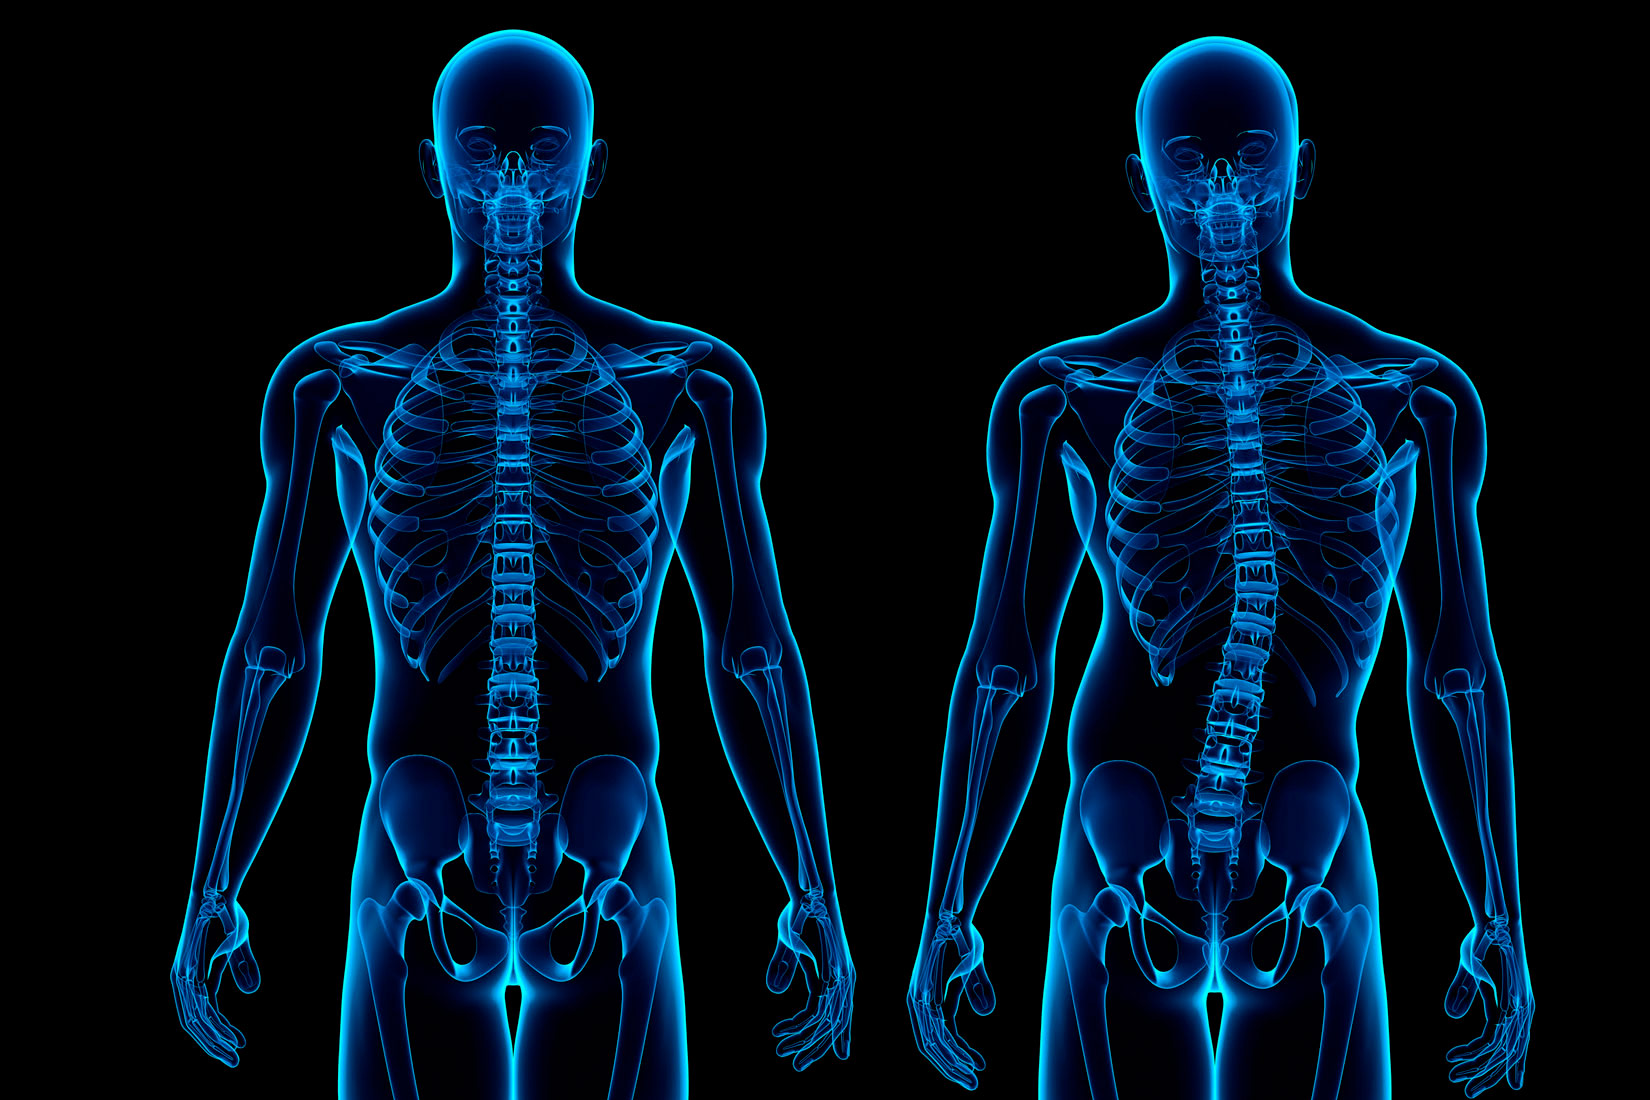

Čovjek u tijelu ima 206 kostiju.

One su povezane u cjelinu i čine kostur.

Kostur je podijeljen na tri cjeline:

- kosti glave

- kosti trupa

- kosti udova

Kostur čovjeka sastoji se od 206 kostiju povezanih u cjelinu.

- kosti glave,

- kosti trupa i

- kosti udova.

Kralježnica nije ravna kao štap.

Ona je blago savijena u obliku dva slova S.

To joj omogućuje nošenje težine glave i vrata.